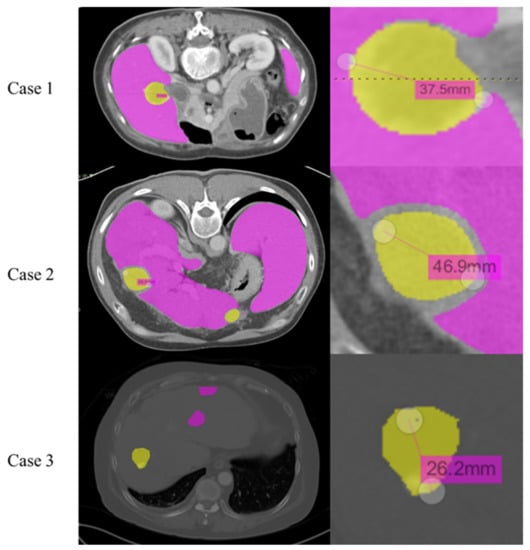

4.5. Misidentification of Tumor Length and Pathological Data Comparison